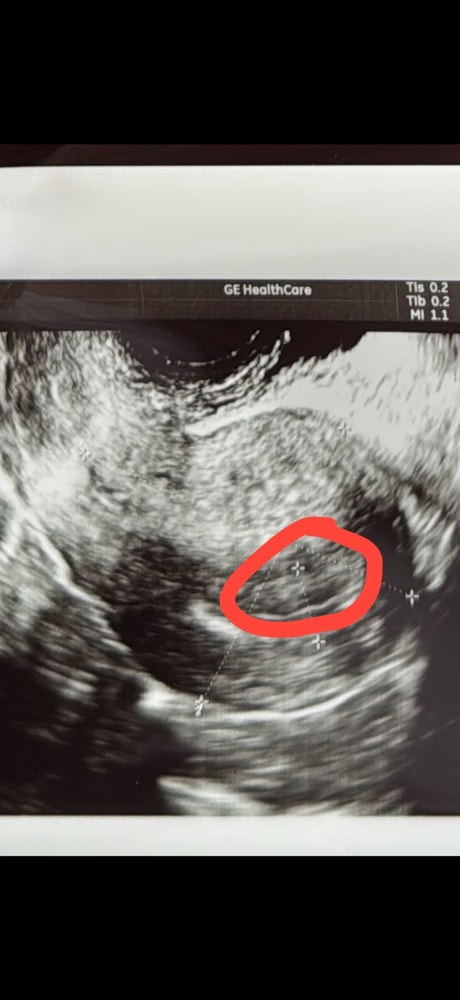

Девочки! подскажите пожалуйста, может ли быть это плодное яйцо? врач сказала в матке ничего не видно ,задержка шесть дней! На сегодня сдада ХГЧ уже 949

Не очень то похоже

Через пару дней повторите узи